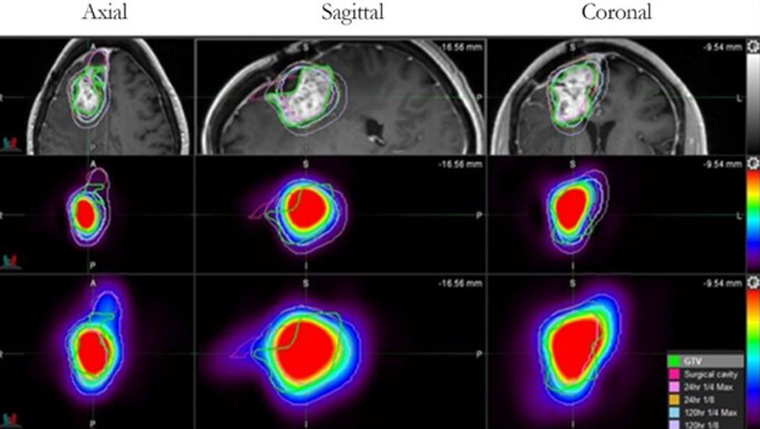

UT Health San Antonio develops drug found to more than double survival time for glioblastoma patients

A drug developed at The University of Texas Health Science Center at San Antonio (UT Health San Antonio) has been shown to extend survival for patients with glioblastoma, the most common primary brain tumor in adults.